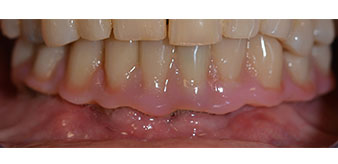

The 64-year-old patient presented with residual dentition of teeth 38, 33 and 43 and a clasp denture in the mandible (Fig. 1 and 2).

Fig. 1